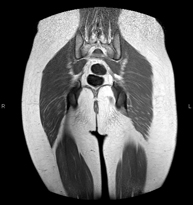

- Gluteal MRI

Examination to study the muscles and tendons that originate at this level, such as the hamstring tendons, which are frequently injured in athletes. It lasts approximately 16 minutes. It is a radiation-free procedure.

- Thigh MRI

Ideal examination for studying injuries to the hamstrings and quadriceps, which are frequently injured in athletes. It also allows for a good assessment of tendons and peripheral nerves. It lasts approximately 20 minutes. It is a radiation-free procedure.